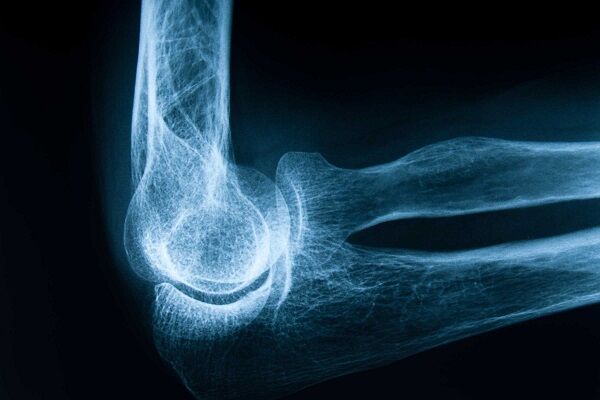

شکستگی استخوان

شکستگی استخوان معمولاً ناشی از ضربه یا سقوط است، اما شکستن مکرر استخوانها بدون وارد شدن نیروی قابل توجه، باید شما را نگران کند. شکستگیها ممکن است حتی با پیچش، خم شدن یا حرکتهای غیرمنتظره رخ دهند. این موضوع میتواند نشاندهنده ضعف استخوانها و پوکی استخوان باشد.